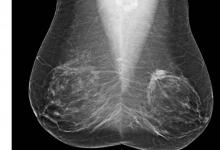

A study of breast cancers detected with screening mammography found that strong family history and dense breast tissue were commonly absent in women between the ages of 40 and 49 diagnosed with breast cancer. Results of the study were presented at the annual meeting of the Radiological Society of North America (RSNA).